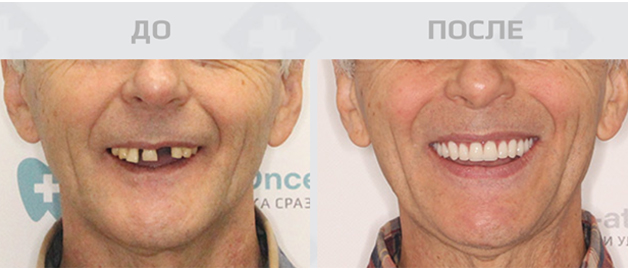

Полная или почти полная адентия, то есть отсутствие зубов — распространенная проблема 21 века. «Болезнь» с каждым годом молодеет, виной тому множество факторов. Это и меняющийся образ жизни, и состояние экологии. Именно вредные вещества оказывают на состояние зубов колоссальное влияние. К счастью, медицина тоже не стоит на месте и оперативно успевает за нарастающей проблемой. Сейчас в арсенале у специалистов — современные технологии и инновационные способы, которые помогают подарить обворожительную улыбку тысячам людей. Самый действенный на данный момент метод — это именно имплантация зубов.

Лишних хлопот можно избежать, если воспользоваться услугами проверенной клиники и провести имплантацию по протоколу немедленной нагрузки. Это значит, что пациенту установят несъемный зубной протез в течение 2-3 дней после вживления имплантатов. Уникальность в том, что жевательная и эстетическая функции зубов будут восстановлены полностью почти мгновенно. Как правило, костная пластика при таком методе не требуется. Так весь процесс лечения вместе с подготовкой займет не более одной недели.

Немедленную нагрузку рекомендуют в основном при множественном или при полном отсутствии зубов. Процедуру можно проводить в любом возрасте при отсутствии общих противопоказаний. Прибегнуть к такой имплантации можно при воспалении пародонта и костной ткани, а также при проседании челюстной кости, которая неизбежно возникает после потери живых зубов.

Имплантация — то, на что бывает сложно решиться, но большинство после процедуры признаются, что зря откладывали поход к врачу так долго. Буквально за несколько дней удастся обзавестись ослепительной улыбкой, снова почувствовать вкус любимой пищи и вернуть себе незабываемое ощущение здоровья полости рта. Реабилитация при удачном исходе проходит максимально быстро. Это важно в том числе — для работающего населения. Для того, чтобы сделать имплантацию, не придется бросать дела или брать долгосрочный отпуск.